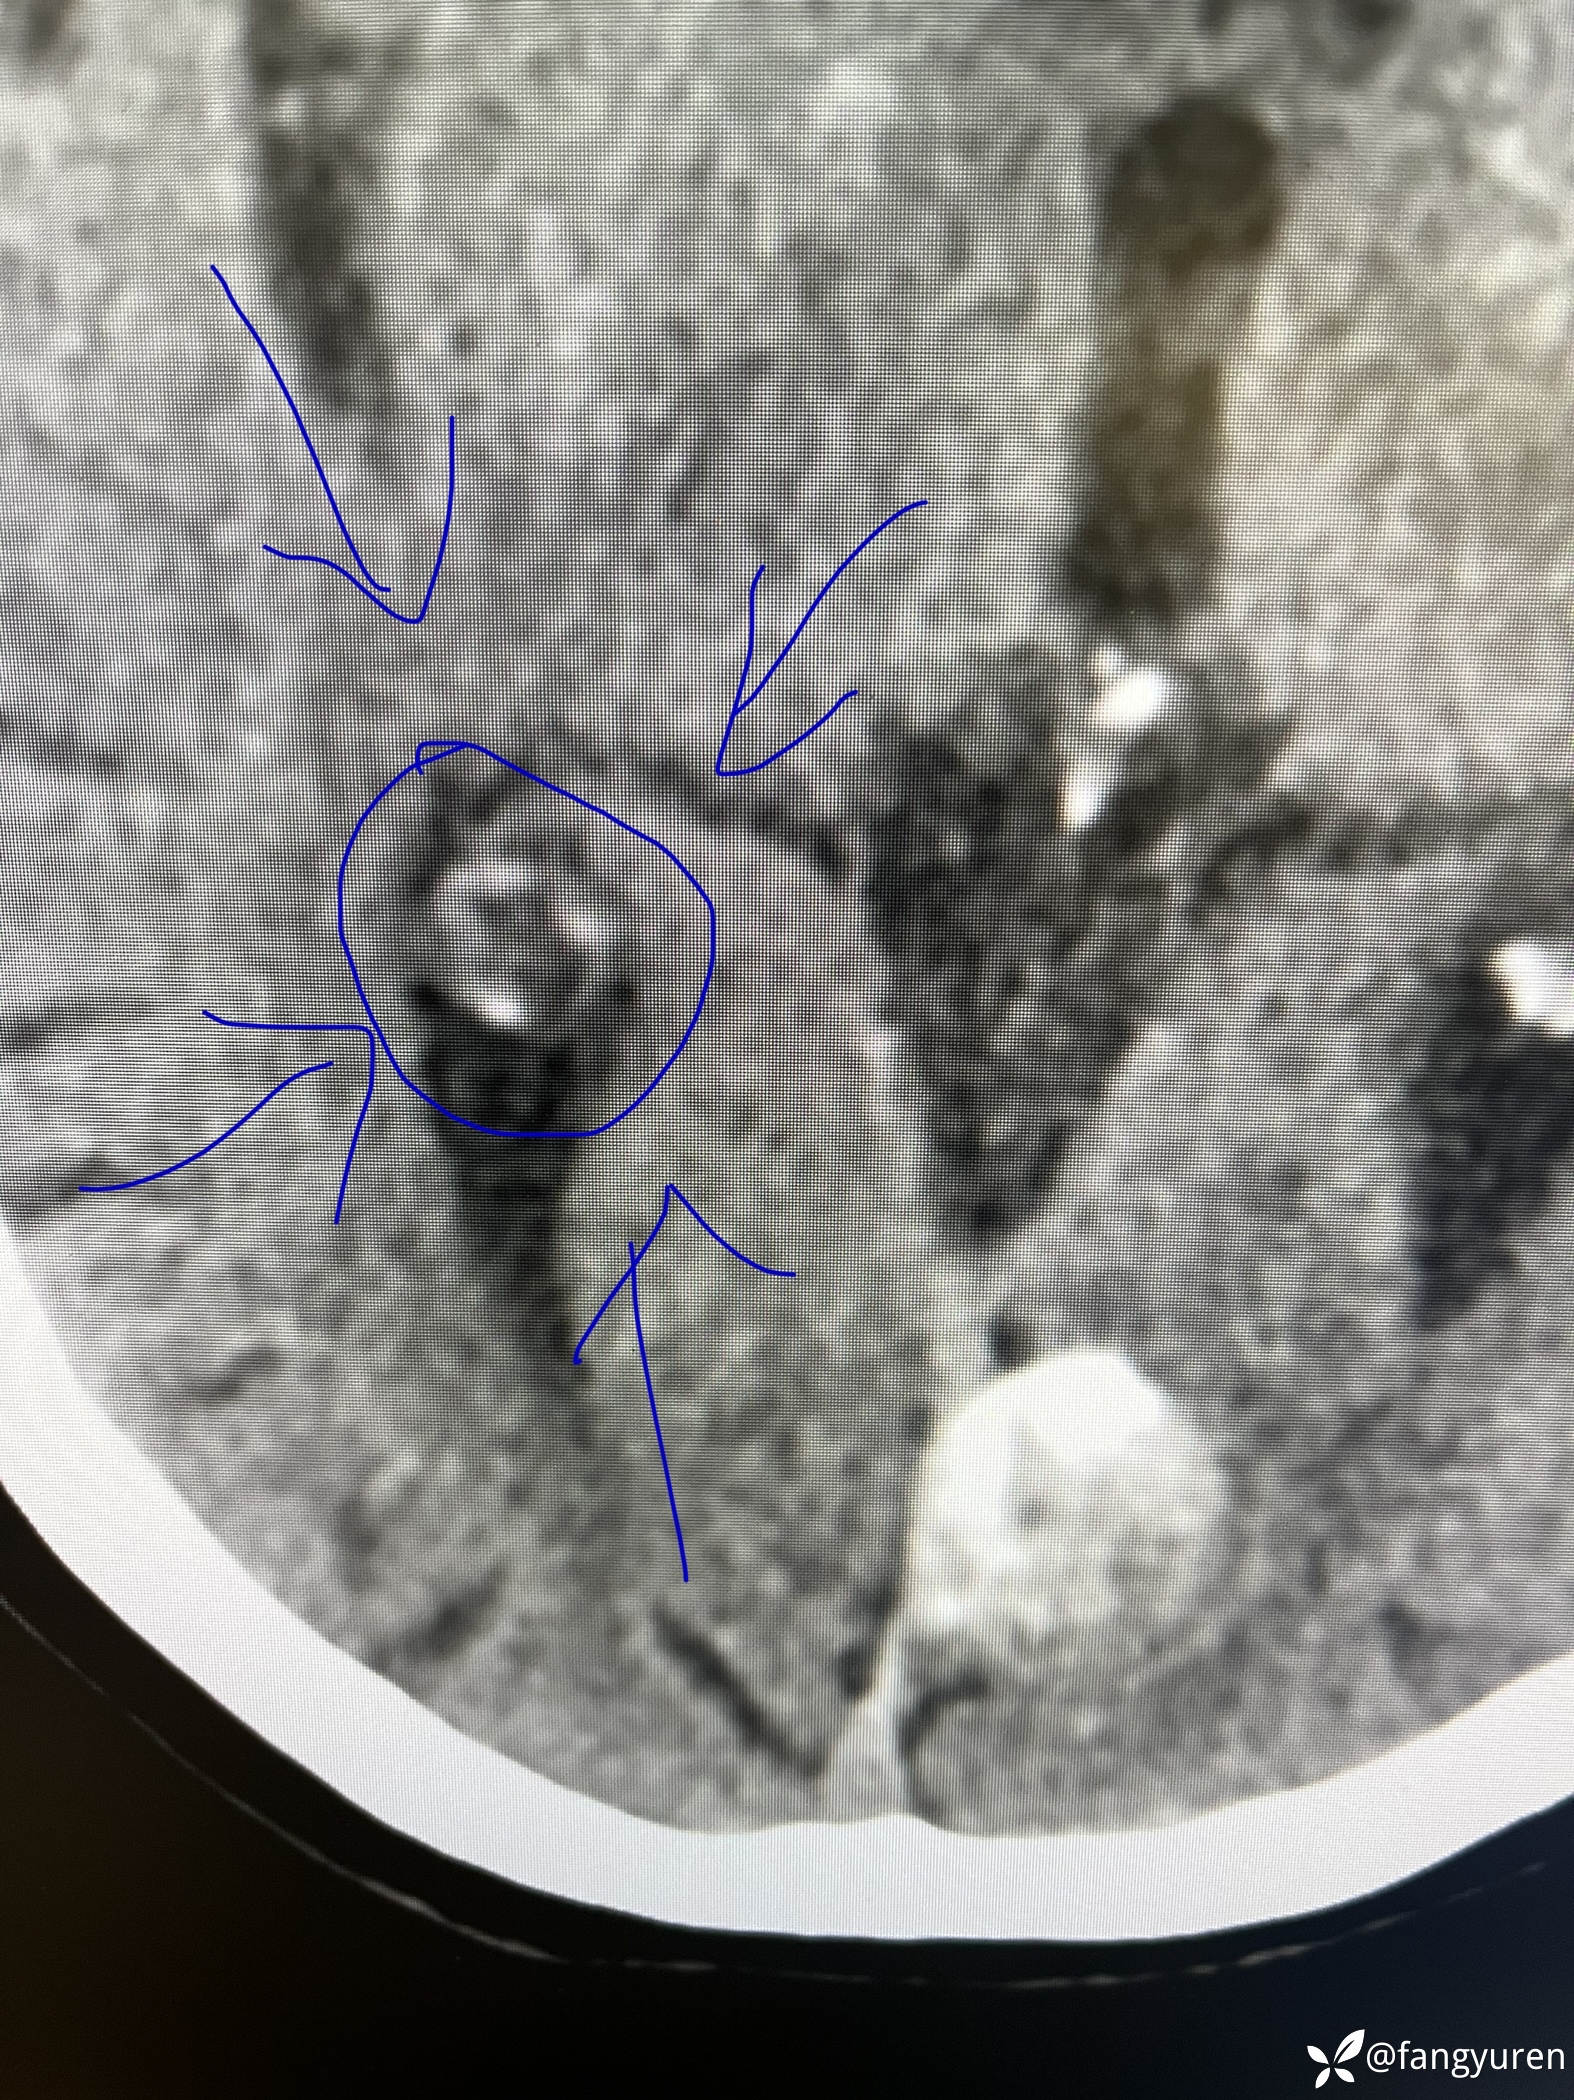

女66,头晕来摄影,发现大脑左侧纵裂旁、左侧额部颅骨下和右侧侧脑室后角见多发类圆形稍高、等、低密度影,部门钙化提示脑膜瘤。如图,蓝圈圈(详细请看视频)所示右侧侧脑室后角见类圆形低密度,周边钙化,考虑是什么,囊状脑膜瘤?多谢老师